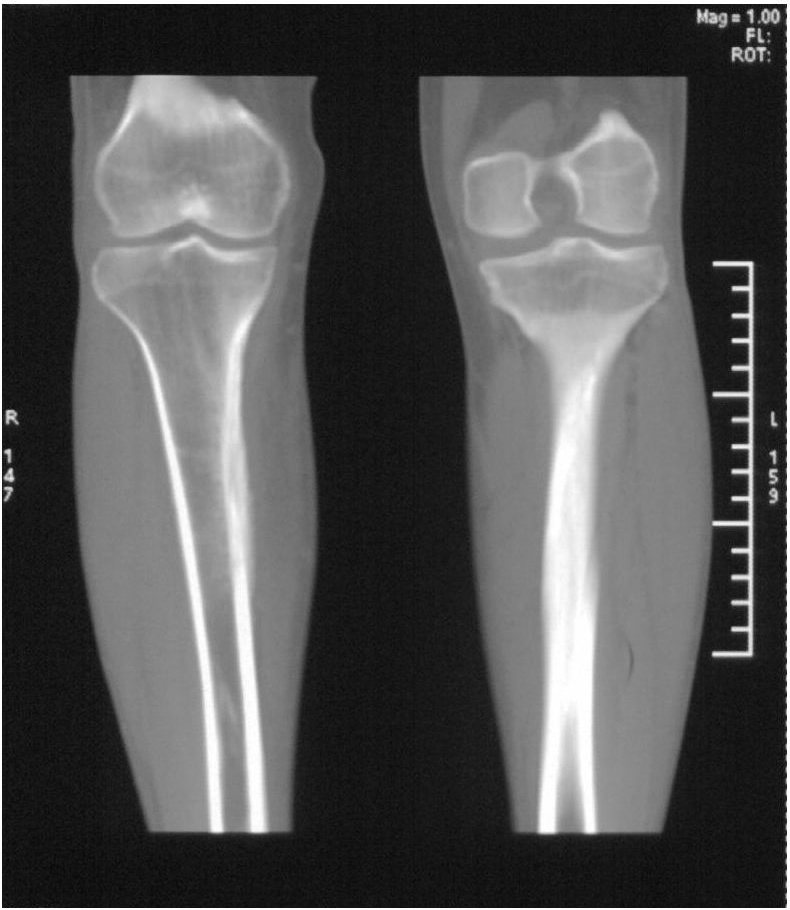

男,42岁。4个月前钢筋钝伤右侧小腿部,当时因无明显外伤,未引起重视。一周后因受伤腿部疼痛,发现肿胀,随后到当地医院进行检查(2008年4月16日)。因未发现骨质异常未引起重视,仅仅进行口服抗生素治疗处理。经过一段时间治疗但未见明显治疗效果在5月29日又进行x线检查,发现有胫骨密度上段密度增高,又进行抗炎治疗,仍未见效果。又在7月3日进行x线检查,仍然报告有胫骨上端密度增高,并建议ct检查。以下是相关检查结果:

髓腔密度呈絮状增高,胫骨上端内侧可见层状骨膜反应,考虑骨髓炎.

髓腔密度呈絮状增高,胫骨上端内侧可见层状骨膜反应,肌间隙模糊,考虑骨髓炎.